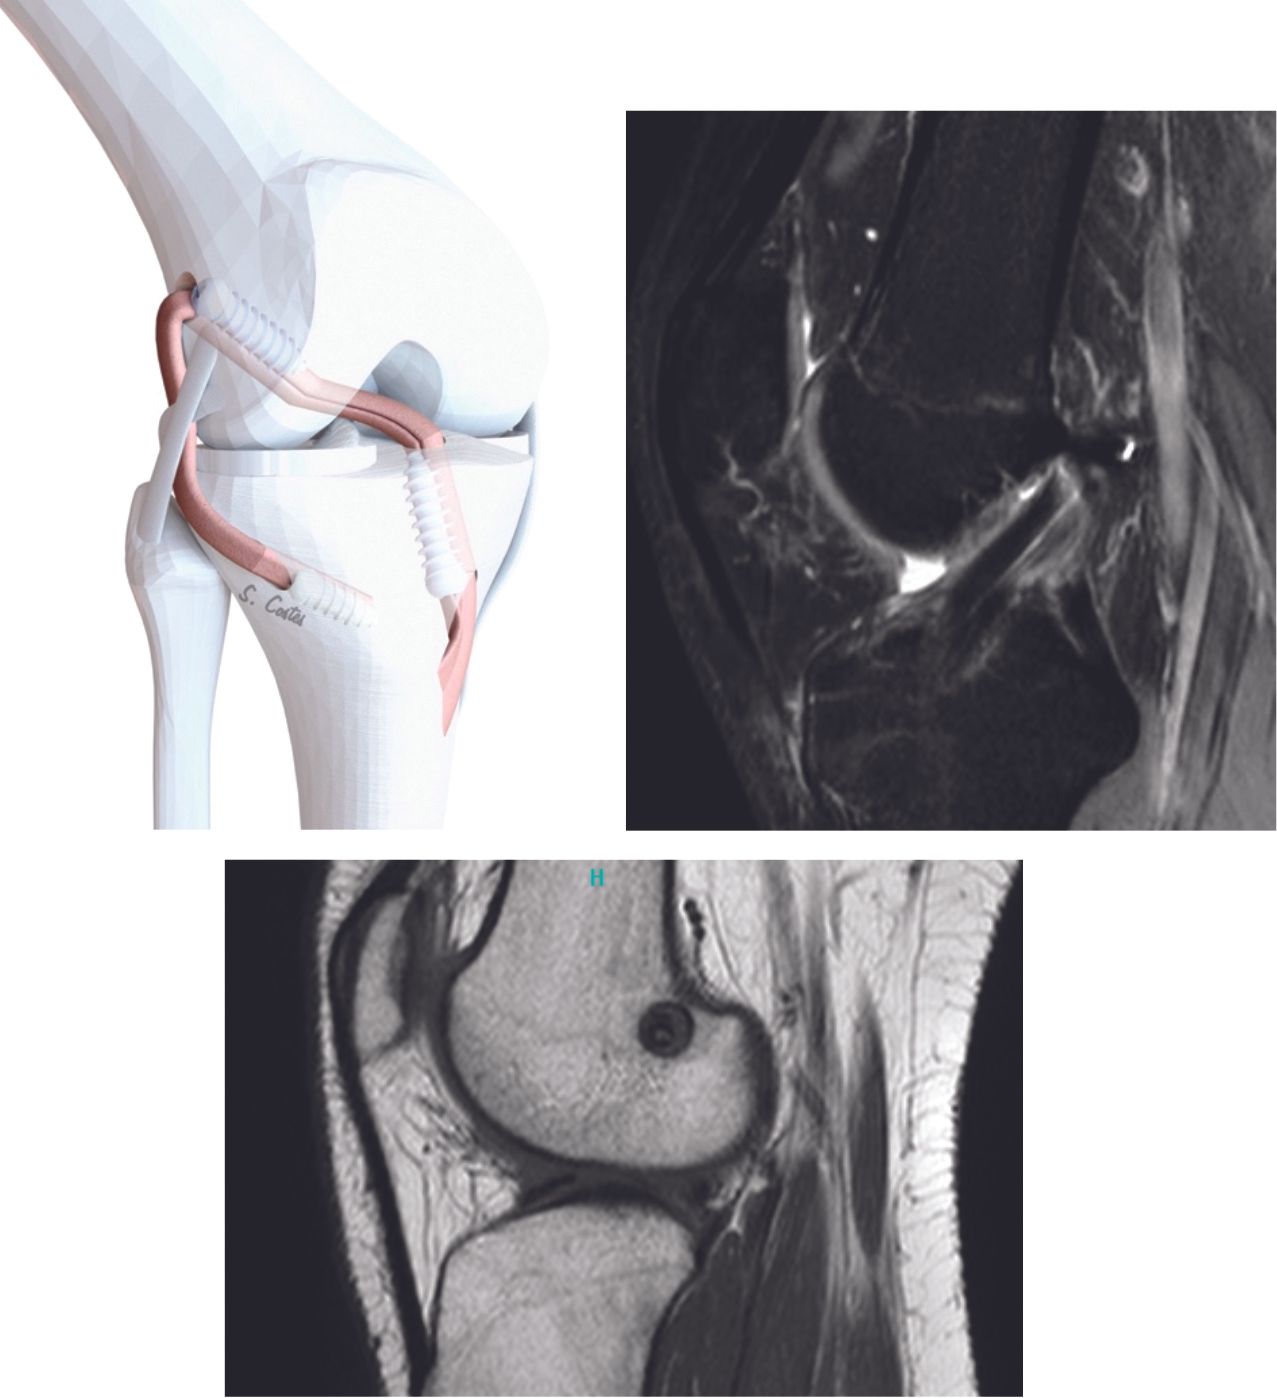

Technique Ligamentoplastie du LCA par une plastie DIDT mixte continue avec plastie latérale originale : description technique et résultats à long terme (10 ans) , Stéphane Costes Service de chirurgie orthopédique et traumatologique, CH Robert Boulin, 112 Rue de la Marne, 33500 Libourne, France 🖂 stephane.costes@ch-libourne.fr , Pierre Meynard Service de chirurgie orthopédique et traumatologique, CH Robert Boulin, 112 Rue de la Marne, 33500 Libourne, France N°300 - Janvier 2021 ● 18 min de lecture